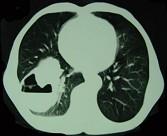

问题 男,76岁,胸痛伴咳嗽,咯血低热1个月,CT检查如图,最可能的诊断为 ( )

选项 A.右下肺脓肿 B.右下肺癌伴空洞形成 C.右下肺囊肿 D.右下肺包虫病 E.右侧包裹性积液

答案 B